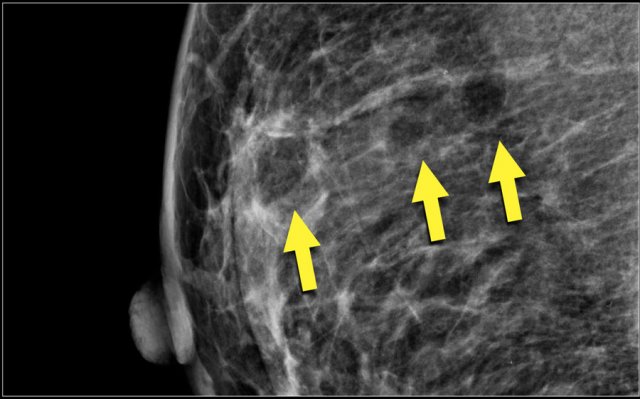

Asymmetries

Findings that represent unilateral deposits of fibroglandulair tissue not conforming to the definition of a mass.

• Asymmetry as an area of fibroglandulair tissue visible on only one mammographic projection, mostly caused by superimposition of normal breast tissue.

• Focal asymmetry visible on two projections, hence a real finding rather than superposition.

This has to be differentiated from a mass.

• Global asymmetry consisting of an asymmetry over at least one quarter of the breast and is usually a normal variant.

• Developing asymmetry new, larger and more conspicuous than on a previous examination.

Here an example of a focal asymmetry seen on MLO and CC-view.

Local compression views and ultrasound did not show any mass.

Here an example of global asymmetry.

In this patient this is not a normal variant, since there are associated features, that indicate the possibility of malignancy like skin thickening, thickened septa and subtle nipple retraction.

Ultrasound (not shown) detected multiple small masses that proved to be adenocarcinoma.

The PET-CT shows diffuse infiltrating carcinoma.